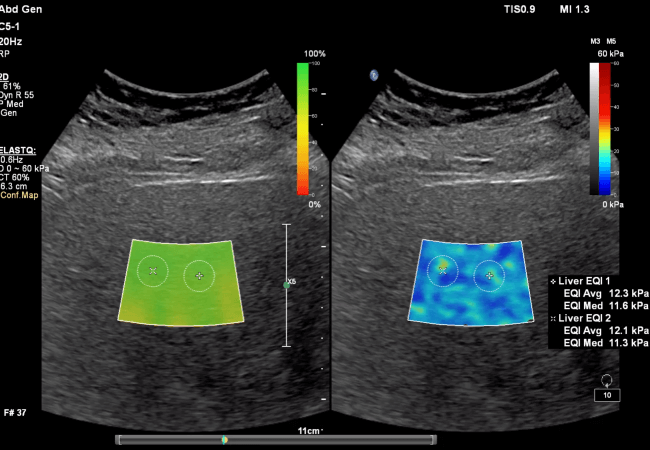

Liver Fat Quantification

Liver fat (visceral fat) is metabolically harmful. This test is performed via ultrasound using FDA-approved software analysis from Philips Healthcare, validated against MRI and liver biopsy to measure liver fat—a key factor in metabolic health and early detection of fatty liver disease.

Liver Fat Image